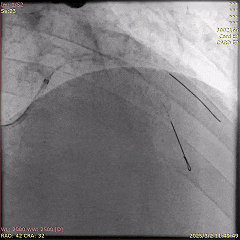

5天后,为患者进行第二次PCI,旨在处理LCx病变。冠脉造影显示,LCx中段模糊病变部位闭塞,术中于病变处植入药物洗脱支架,成功实现血管再通。

第二次PCI中的冠脉造影